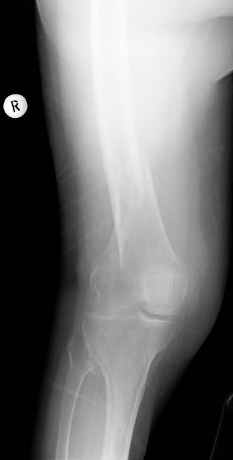

Уважаемые коллеги, Было бы интересно узнать вашу тактику при остеосинтезе этого перелома.

С уважением Вальдемар.